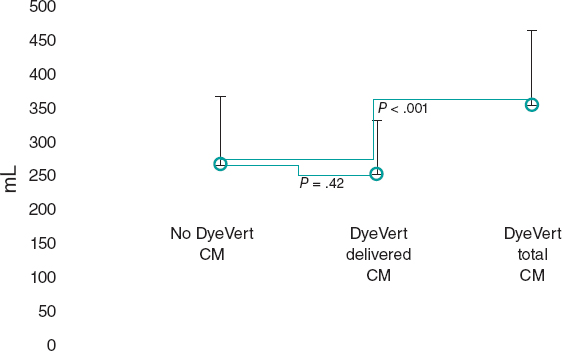

Diagnostic study of a CTO

The rate of success is associated with a good diagnostic study to determine the vessel architecture in the occlusion region. It is important to locate the occlusion proximal edge and see if there are microchannels or proximity collaterals, but we do not need to use more than 15 images per second; however, at times it is necessary to increase the volume and pressure of contrast injection. The catheters should be perfectly placed inside the coronary ostia to avoid losing contrast through the aorta. Contralateral injections are also crucial (sometimes collateral circulation is homolateral) to see the occlusion final edge, the anatomy of the distal bed, make correct assessments of the collaterals, and determine whether the retrograde interventional procedure is possible.

There is a special situation when the anterior descending artery receives collateral circulation through Viuessens’ arterial ring35 where the right conus artery may anastomose with the left conus artery that exits the proximal or medial segment of the anterior descending artery. There are times when this conus artery exits an independent ostium of the right coronary artery and needs to be cannulated using a mammary artery catheter with a specifically curved tip or a hockey stick design. It is advisable to perform a coronary CT scan to evaluate the architecture of the occlusion in patients undergoing aortocoronary revascularization surgery, with high J-CTO scores or aorto-ostial occlusions.